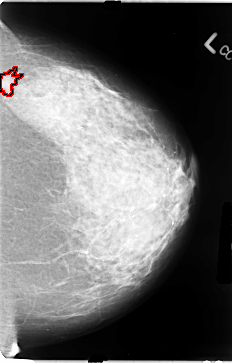

B_3078_1.LEFT_CC

FILE: B_3078_1.LEFT_CC.OVERLAY

TOTAL_ABNORMALITIES 1

ABNORMALITY 1

LESION_TYPE MASS SHAPE IRREGULAR MARGINS ILL_DEFINED

ASSESSMENT 2

SUBTLETY 2

PATHOLOGY MALIGNANT

TOTAL_OUTLINES 1

BOUNDARY